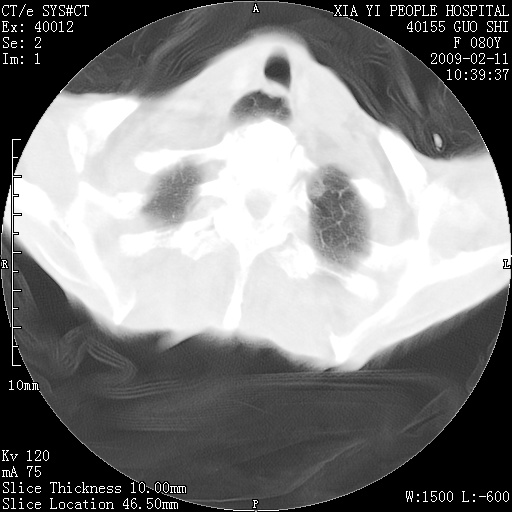

以下是引用随光逐影在2009-2-16 16:34:00的发言:[br]1)考虑右前纵隔皮样囊肿。2)双侧少量胸腔积液。

以下是引用zjzjr在2009-2-16 17:30:00的发言:[br]支持囊性畸胎瘤 双侧少量胸腔积液。